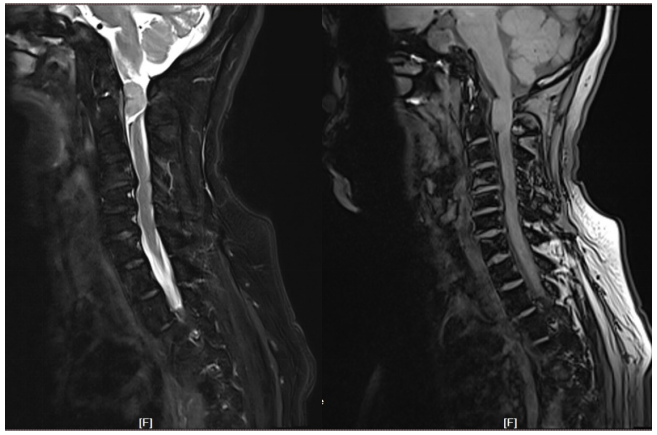

病例1 女性 43岁

患者以“腰部不适1月余”为主诉入院,专科查体双下肢各肌群肌力Ⅳ级,无明显病理征。

结合患者影像学资料,病变部位较长,椎体慢性受压改变,患者症状较轻,考虑病程较长,倾向于良性病变可能;T1等信号,T2混杂信号,局部脊髓信号增粗,髓内肿瘤可能,倾向于室管膜瘤。

行椎管内肿瘤切除+椎板回植术,术后患者下肢肌力正常,术前不适症状明显改善。